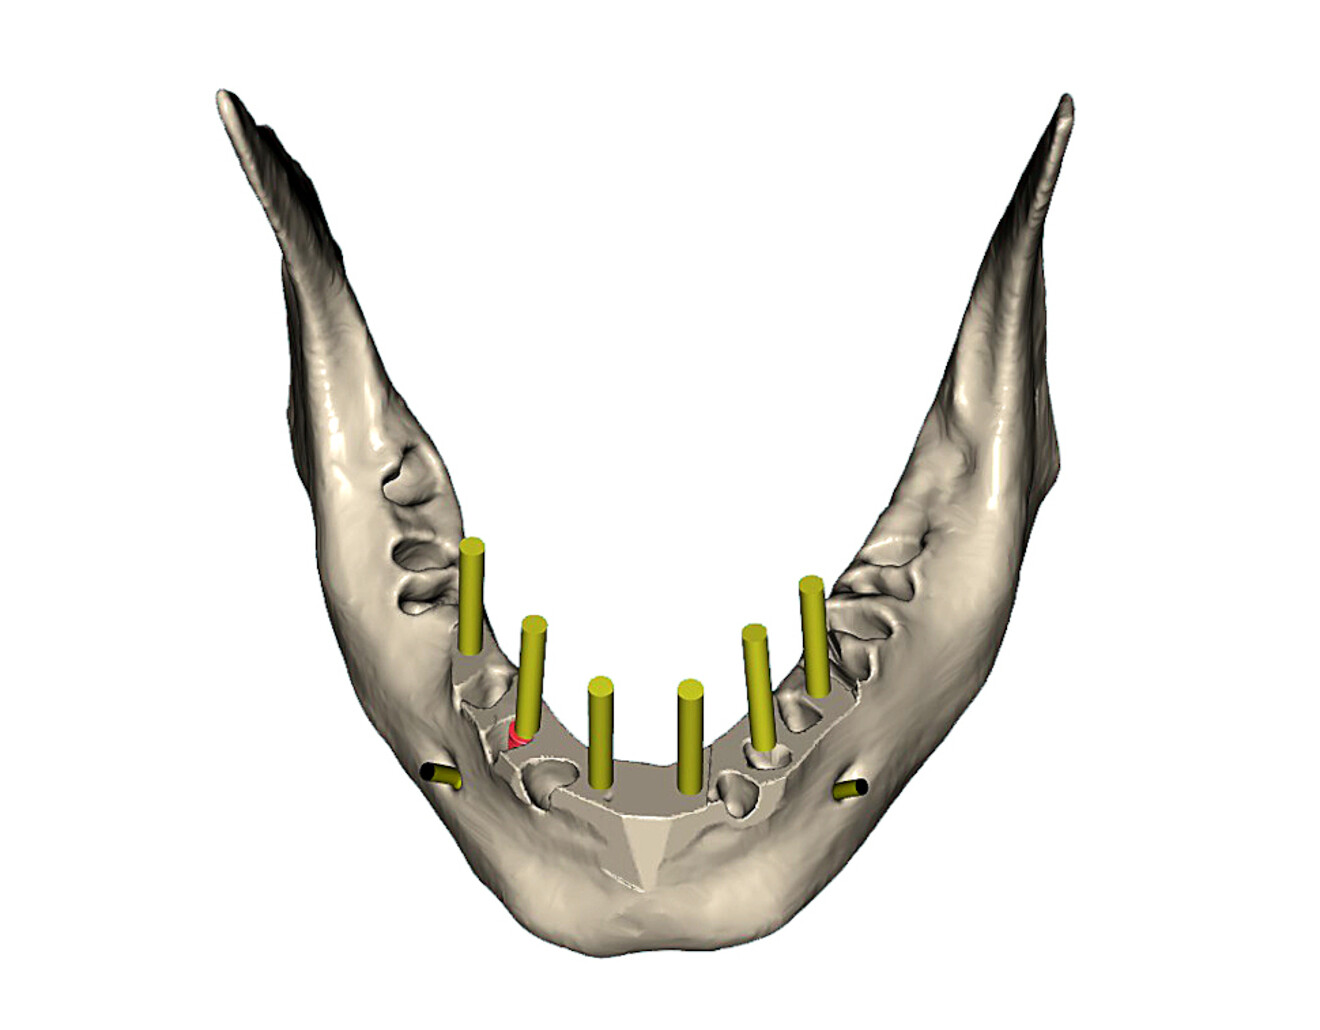

Fig. 14a: Occlusal view of the simulated extraction sockets in the mandibular bone.

Fig. 14b: Simulation of parallel implants in the mandible with yellow abutment projections

The mandibular arch followed a similar surgical protocol utilising a bone-borne surgical guide after tooth extraction and bone reduction. The advanced bone and tooth segmentation illustrated the severe bone loss almost to the apex of many of the mandibular roots (Fig. 13a). Using selective transparency, the roots and bone could be closely evaluated (Fig. 13b). 3D volumetric reconstruction simulating the post-extraction bone helped provide a unique view of the mandibular bony anatomy (Fig. 14a) and aided in finalising the location of each implant (Fig. 14b).